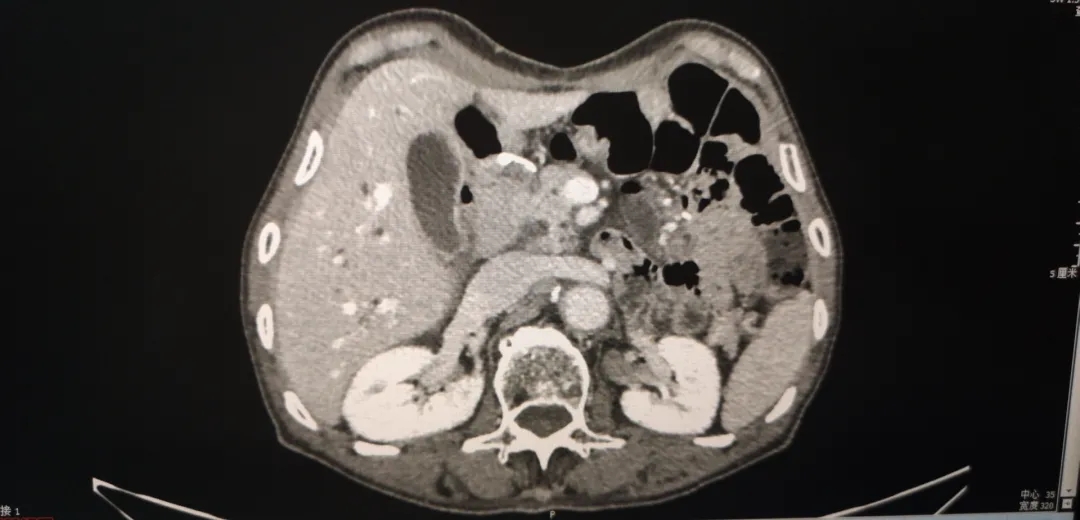

2020.4腹盆CT

2020-4增强CT:与2019.11.25腹盆片比较,整体未见明显变化。